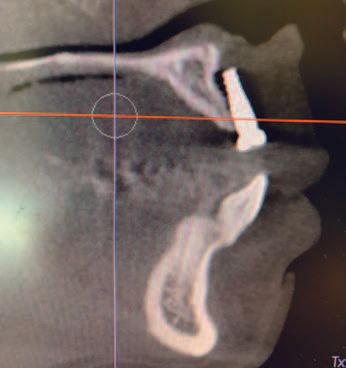

After taking a CAT screen Dr. Mark noticed that #9 was not placed in bone but was free floating in the soft tissue (Figures: A, B) and it too would fail. The patient informed Dr. Mark that she was told that she would need more bone grafting followed by another six months of waiting before new implants could be placed by the original dentist. Commenting on the proposed treatment plan, Dr. Mark said: “Upon examination of the patient and detailed review of the 3D anatomy of the anterior region of the maxilla, I concluded that a ridge splitting technique would be the best option moving forward.” He went on to inform the patient that if the ridge spitting was successful, he would be able to place the implants at the same time. The patient agreed to the procedure and was amazed that the entire process could be completed in one visit.